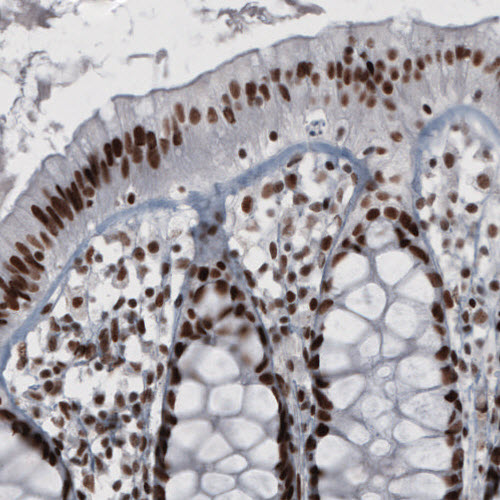

Immunohistochemical staining of human fallopian tube shows strong nuclear immunoreactivity in glandular and connective tissue cells.